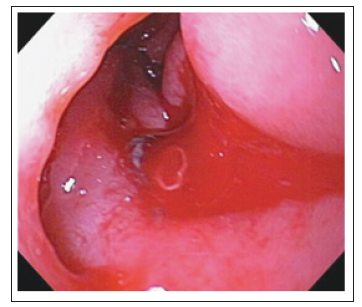

There are many modalities that may aid in the diagnosis of an AEF, but without strong clinical suspicion, these modalities may be futile. The initial evaluation of AEF should be started by esophagogastroduodenoscopy(EGD) to identify the cause of bleeding. The whole duodenum must be investigated in EGD because of the frequent location of the AEF in its 3rd and 4th parts. Findings suggestive of AEF on EGD include visible graft, bleeding, adherent clot, or ulcer or pulsatile mass (Figures 3 & 4). CT scan has 30-61% sensitivity in identifying PAEF, and 90% sensitivity and specificity in identifying SAEF. In addition to identifying the location, it may aid in the identification of an infection or abscess formation if present. Signs found on CT imaging may be gas shadow in or around the graft (sensitivity 40% and specificity 100%), focal wall inflammation and thickening, visible graft (sensitivity 22% and specificity 100%), soft tissue collection around the aorta (specificity 92% and sensitivity 90%), swelling or hematoma around the graft, intravenous contrast within the GI lumen or around the aorta, loss of calcification or tear in the aortic wall (specificity 75% and sensitivity 89%), pseudoaneurysm, and duodenal hematoma (Figures 5 & 6).

Figure 3:Visible graft with bleeding on (EGD)..

Figure 4:Push enteroscopy showing aortoenteric fistula with bleeding (arrow).